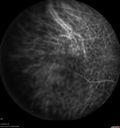

88 year old female with melanosis oculi and 2.5 mm elevated choroidal melanoma. She also has AMD with geographic atrophy. The right eye is the better eye. The left eye had a macular hemorrhage from wet AMD and breakthrough vitreous hemorrhage.